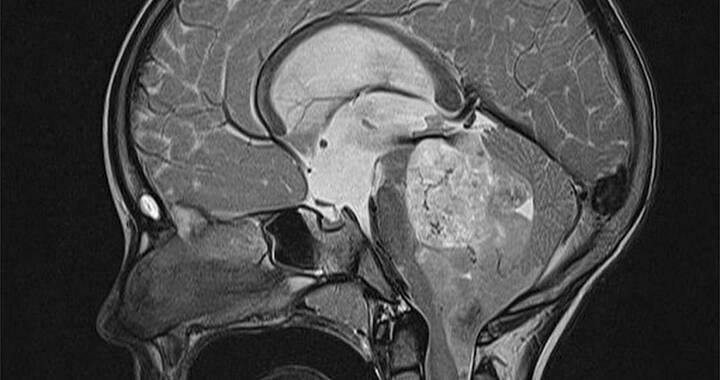

MRT-Bild von einem menschlichen Gehirn mit erkennbarem helleren Tumor.